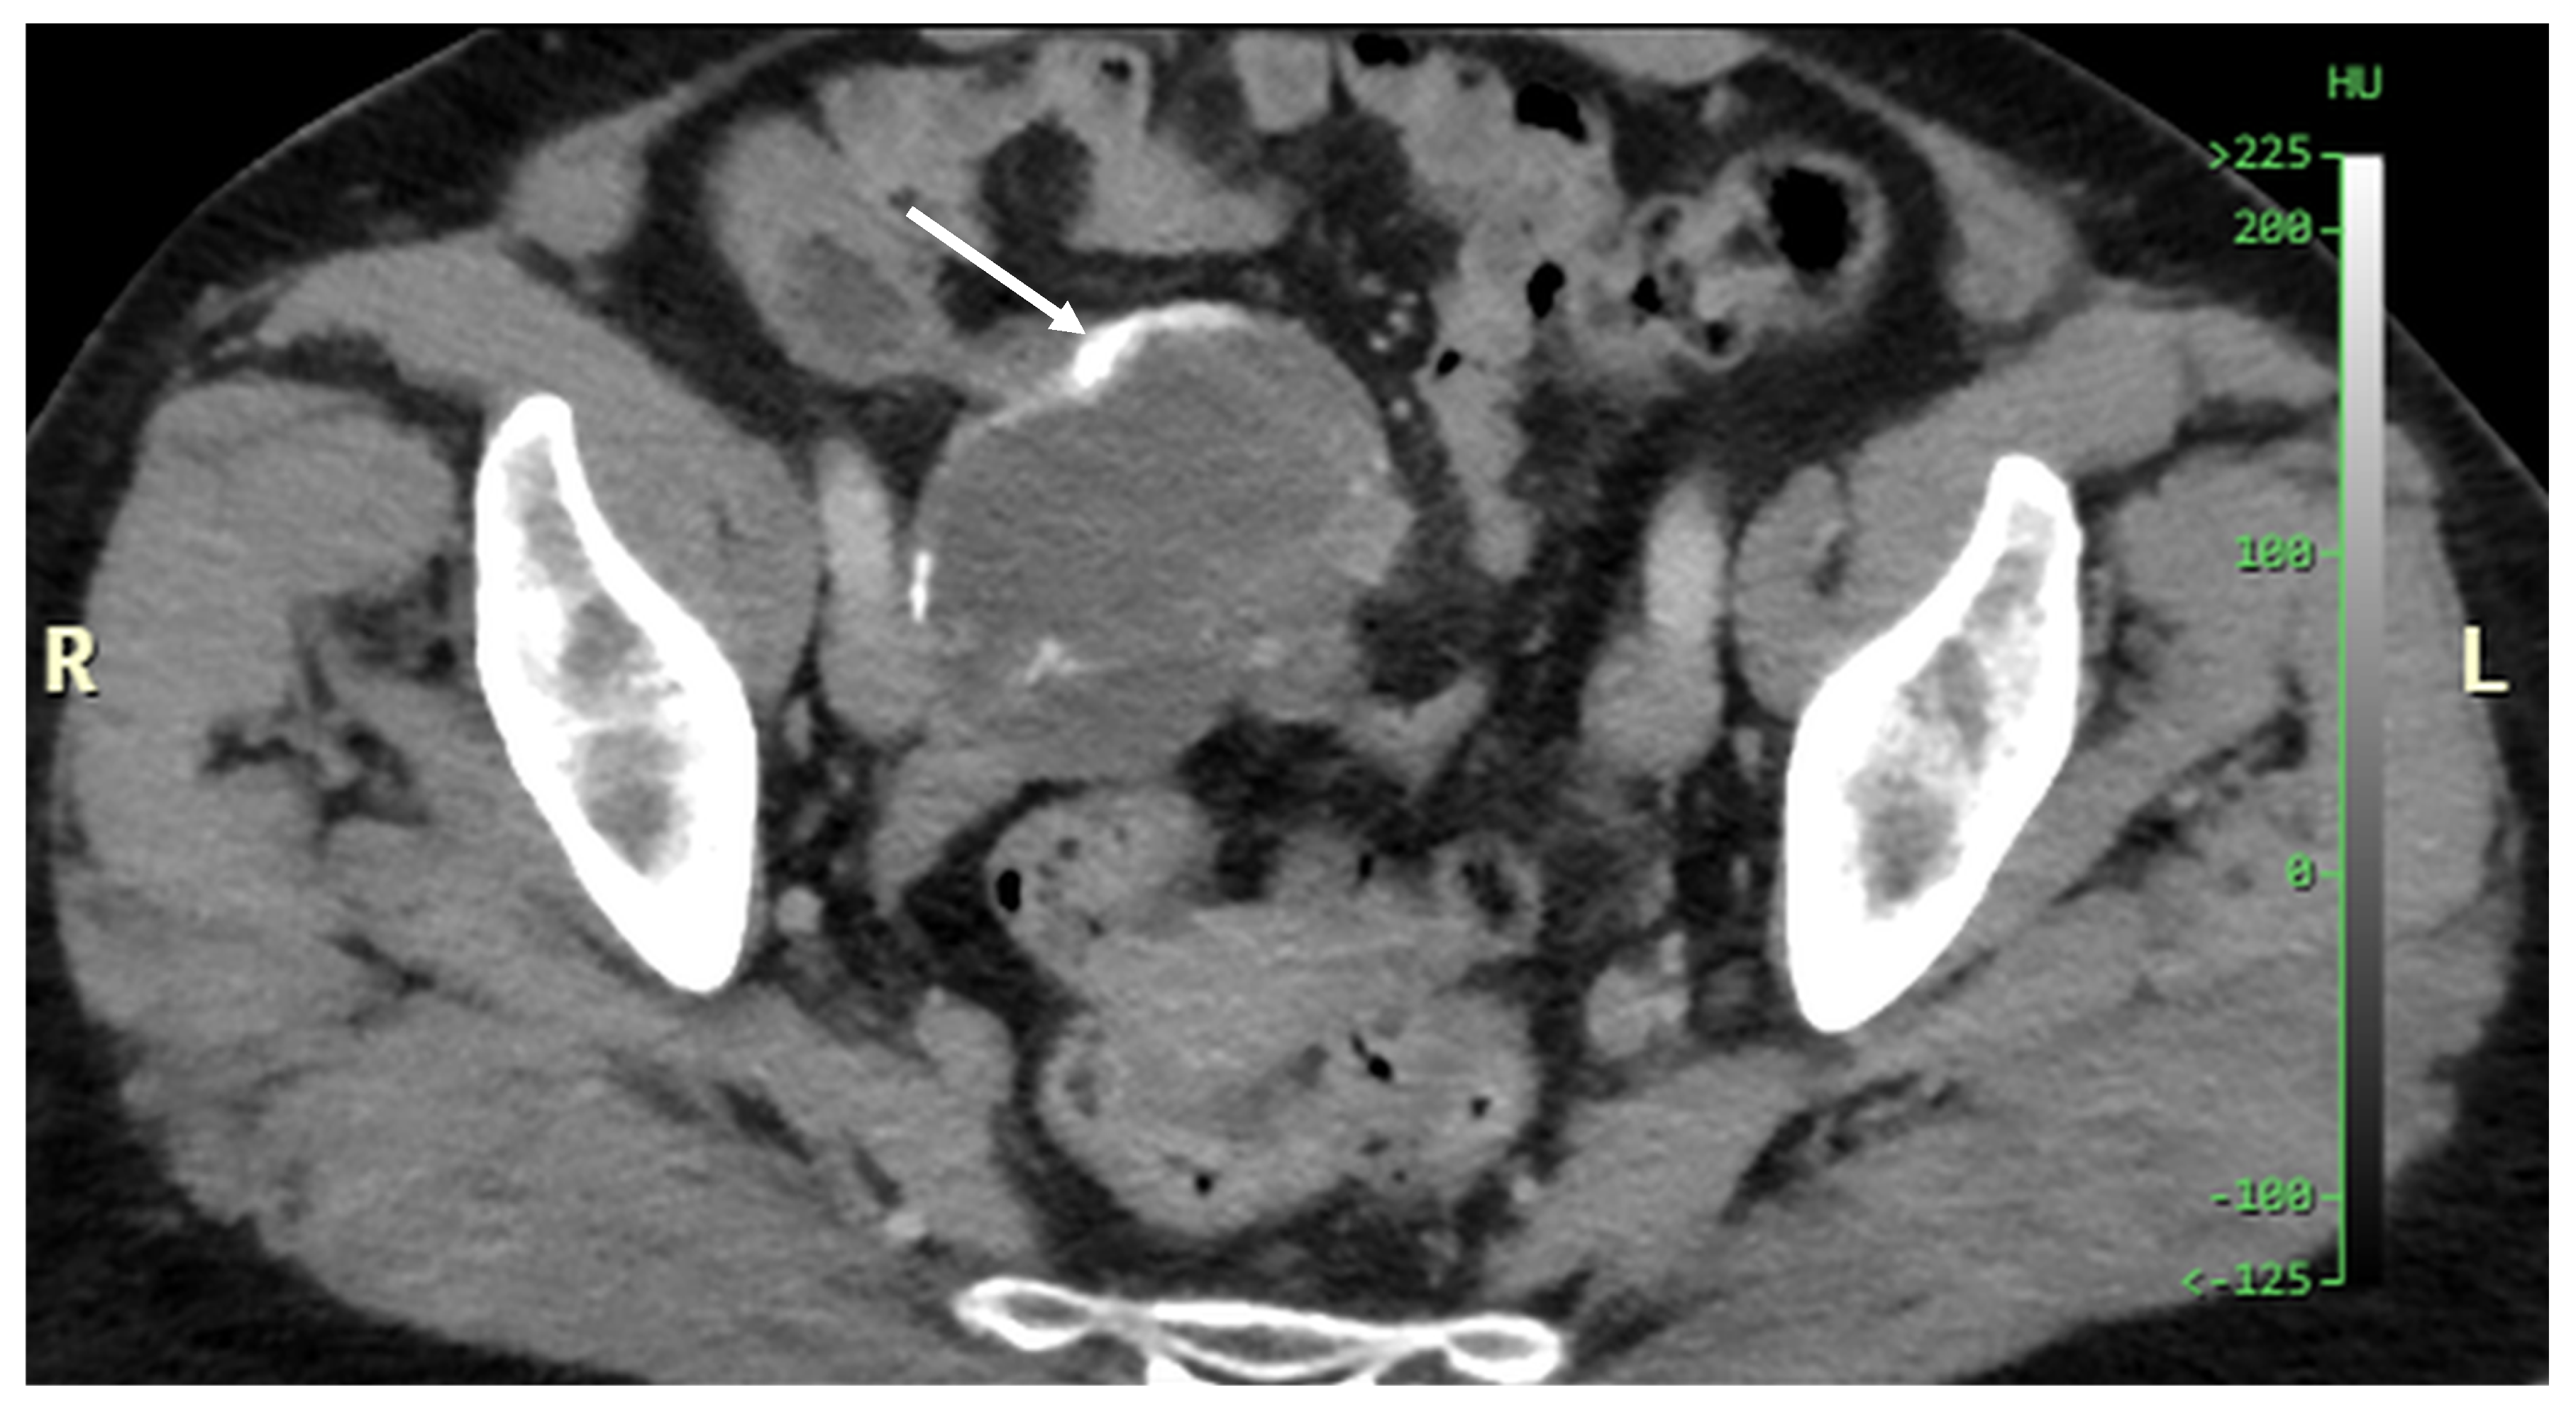

Figure 20. Recurrence four years after CRS + HIPEC. Mucinous tumor around the liver and in the porta hepatis (arrows). This patient was successfully treated with repeated CRS + HIPEC. (CT, portal phase, coronar plane).

Patients who have undergone cytoreductive surgery and HIPEC due to pseudomyxoma peritonei should be followed up with imaging studies at regular intervals. Recurrence may occur after several years (Figure 20 and Figure 21).